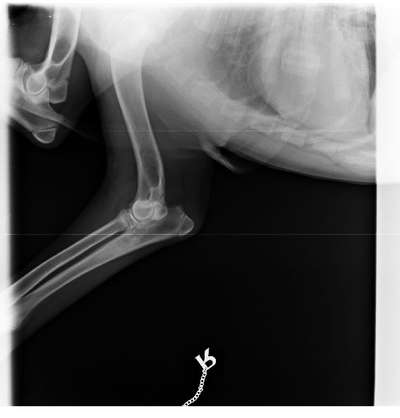

Mein Hund, weißer Schäferhund 6 Monate, fing nach einem Sturz am Folgetag an zu humpeln. Er schont immer mal wieder die Pfote durch anheben. Da das Wochenende vor uns lag, hab ich erst 3 Tage später einen Termin beim Tierarzt bekommen. Der Arzt stellt eine Druckempfindlichkeit am Radius fest. Er wollte gerne Röntgen. Das Röntgenbild gefiel ihm aber nicht und wollte gerne einen Kollegen im Rat fragen. Ich hab aber leider vor dem Wochenende noch nichts gehört und mache mir eine Kopf. Wir haben eine Behandlung mit Metacam gestartet. Einmal angespritzt und ich gebe es jetzt täglich einmal. Ich würde ihnen gerne mal das Röntgenbild zeigen und um ihre Meinung bitten. Ich sehe ein leichte Verschattung ( Panostitis?) kann aber am Gelenk selbst nichts erkennen. Das Bild wurde nicht unter Vollnarkose gemacht

Zunächst einmal möchte ich betonen, dass Röntgenbilder vom Foto nur sehr eingeschränkt bis garnicht zu beurteilen sind. Aus diesem Grund interpretieren wir hier eigentlich keine Röntgenaufnahmen. Zudem sind auf der Aufnahme die Unterarmknochen nicht vollständig abgebildet, was die Interpertation der Aufnahme zusätzlich einschränkt.

Der Teil des Radius, der auf der Röntgenaufnahme erkennbar ist, sieht zunächst unauffällig aus. Im proximalen (oberen) Bereich der Ulna ist eine leichte Verschattung (stellt sich im Röntgen hell dar) im Bereich des Markraums (Inneres des Knochens) zu sehen. Eine solche Verschattung kann verschiedene Ursachen haben. Eine Panostitis ist ein möglicher Grund.

Um die Röntgenaufnahme genau beurteilen und interpretieren zu können bedarf es aber der Originalaufnahmen. Ich würde dir somit empfehlen, dich nach dem Wochenende mit deinem Tierarzt in Verbindung zu setzten.